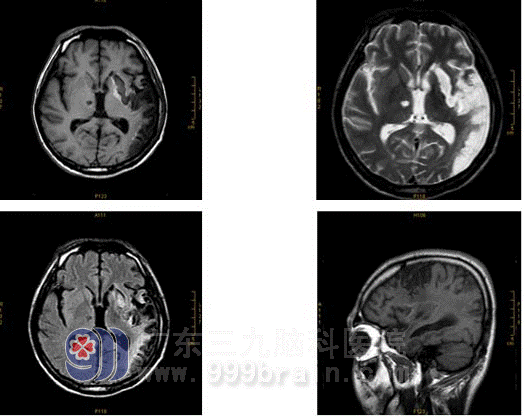

He reviewed a month later:

The colloid substance around infarction section increased. MRA showed his left brain still had artery emphraxis.